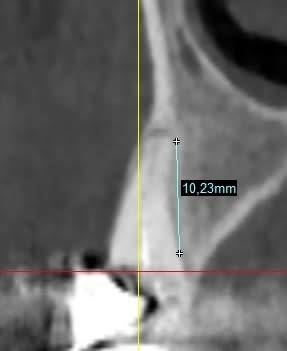

Je vous met la pano complète ainsi que des détails qui je l'espère seront suffisants pour vous faire une idée.

Les hauteurs que j'ai pu indiquer comporte aussi de la dentine infiltrée, pardonnez moi de le préciser.